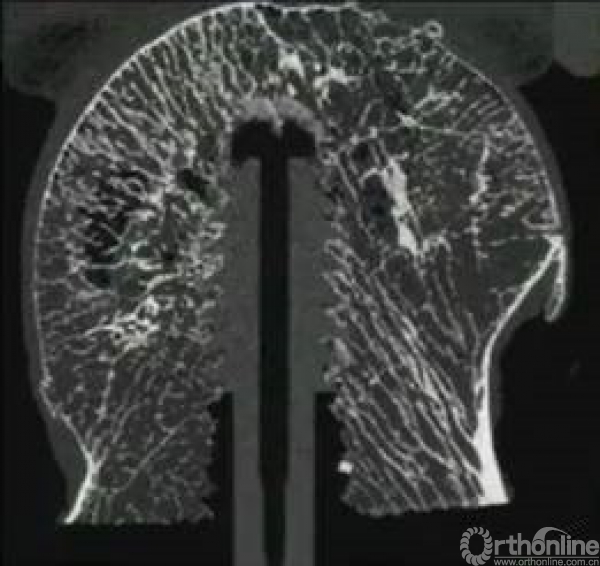

骨质疏松也会影响内固定在股骨头内的稳定性。

疏松的骨质不适合使用螺钉稳定,而更适合螺旋刀片打压。

同时,双钉可以更好的预防头钉切出。